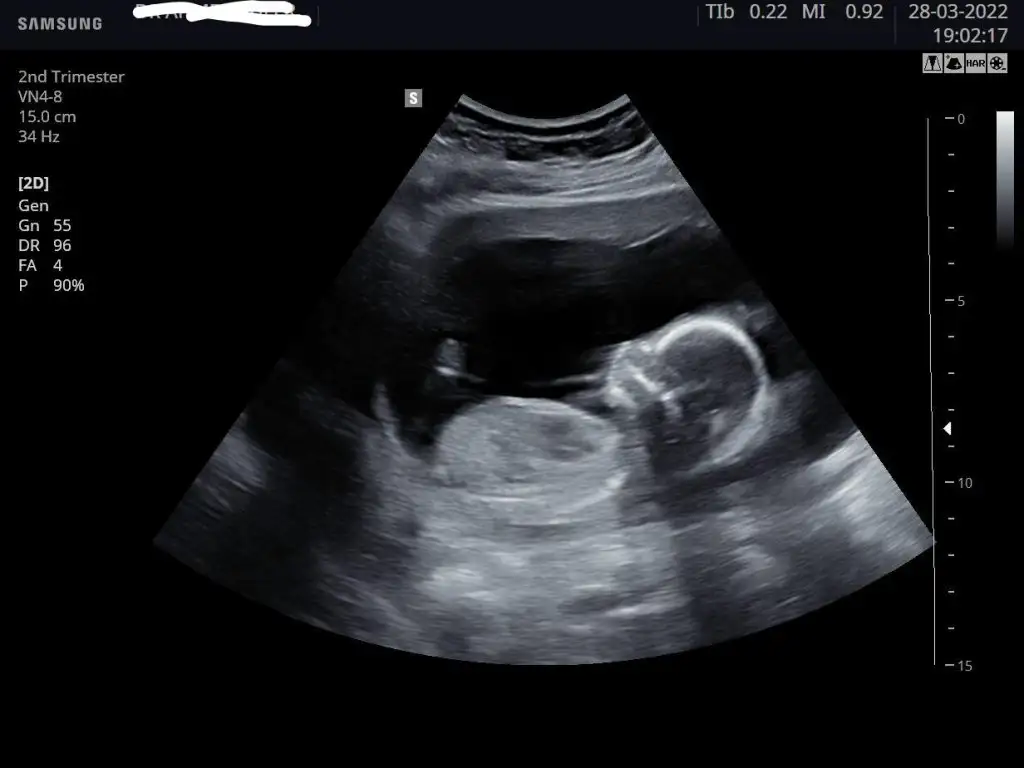

Kızlar dün geçmeyen sancıyla acile koştum. İdrar yolu enfeksiyonu dediler, ağrı öyle siddetliydi ki kendi doktoruma da gitmek istedim. Bebek de her şey yolunda çok şükür, hatta yine uyumuyor , tekme atiyordu bu kez. Detaylı ultrason randevumu da aldım gitmişken, bu arada yüzde 90 kızım oluyor 👧🏻💗

Bu kadar yakalayabildi, tekmelerden fırsat bulunca🤣, 7 Nisan'da enfeksiyon sonrası kontrole gidicem, belki o zaman poz verir koca göbüşlü 🤗